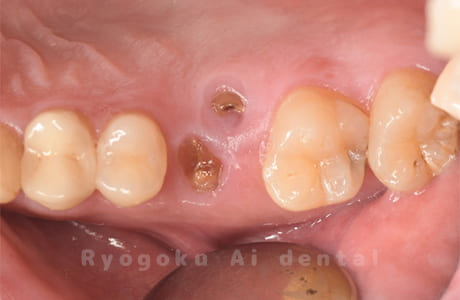

Case26

歯軋りが原因で奥歯を割ってしまった患者様です。下の親知らずを移植し、その際にサイナスリフトを行いました。問題なく経過し、患者様も大変満足されていました。